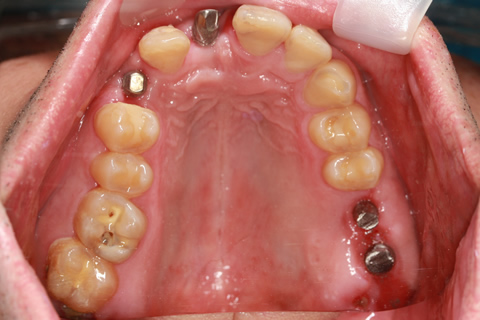

症例4

治療前

治療後

- 年齢・性別

- 60歳

- 治療期間

- 6ヶ月

- 抜歯

- 残根抜歯のみ

- 治療費

- 184.8万円

- 備考

- 右上5.6 右下5 左下4.5.6欠損

- 治療内容

- 6本のインプラントを右左側に2回に分けて埋入

- 施術の副作用(リスク)

- オペによる知覚障害。インプラントによる歯肉炎。インプラント脱落。